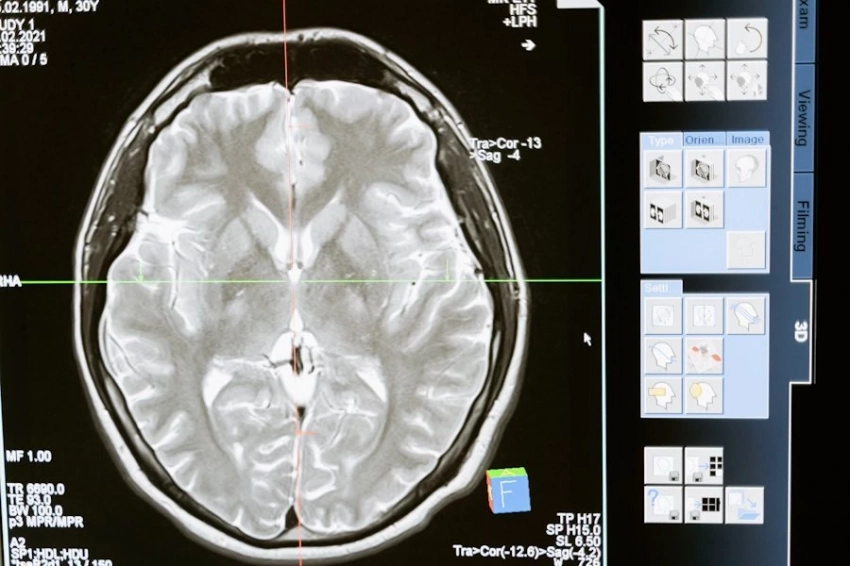

Фото из открытых источников

Ученые из Memorial Sloan Kettering Cancer Center (США) добились значительного прорыва в лечении глиобластомы — одной из самых агрессивных форм рака мозга. Ими была идентифицирована молекула глиоцидин, способная избирательно уничтожать клетки глиобластомы, не повреждая при этом здоровые ткани организма, сообщает Nature.